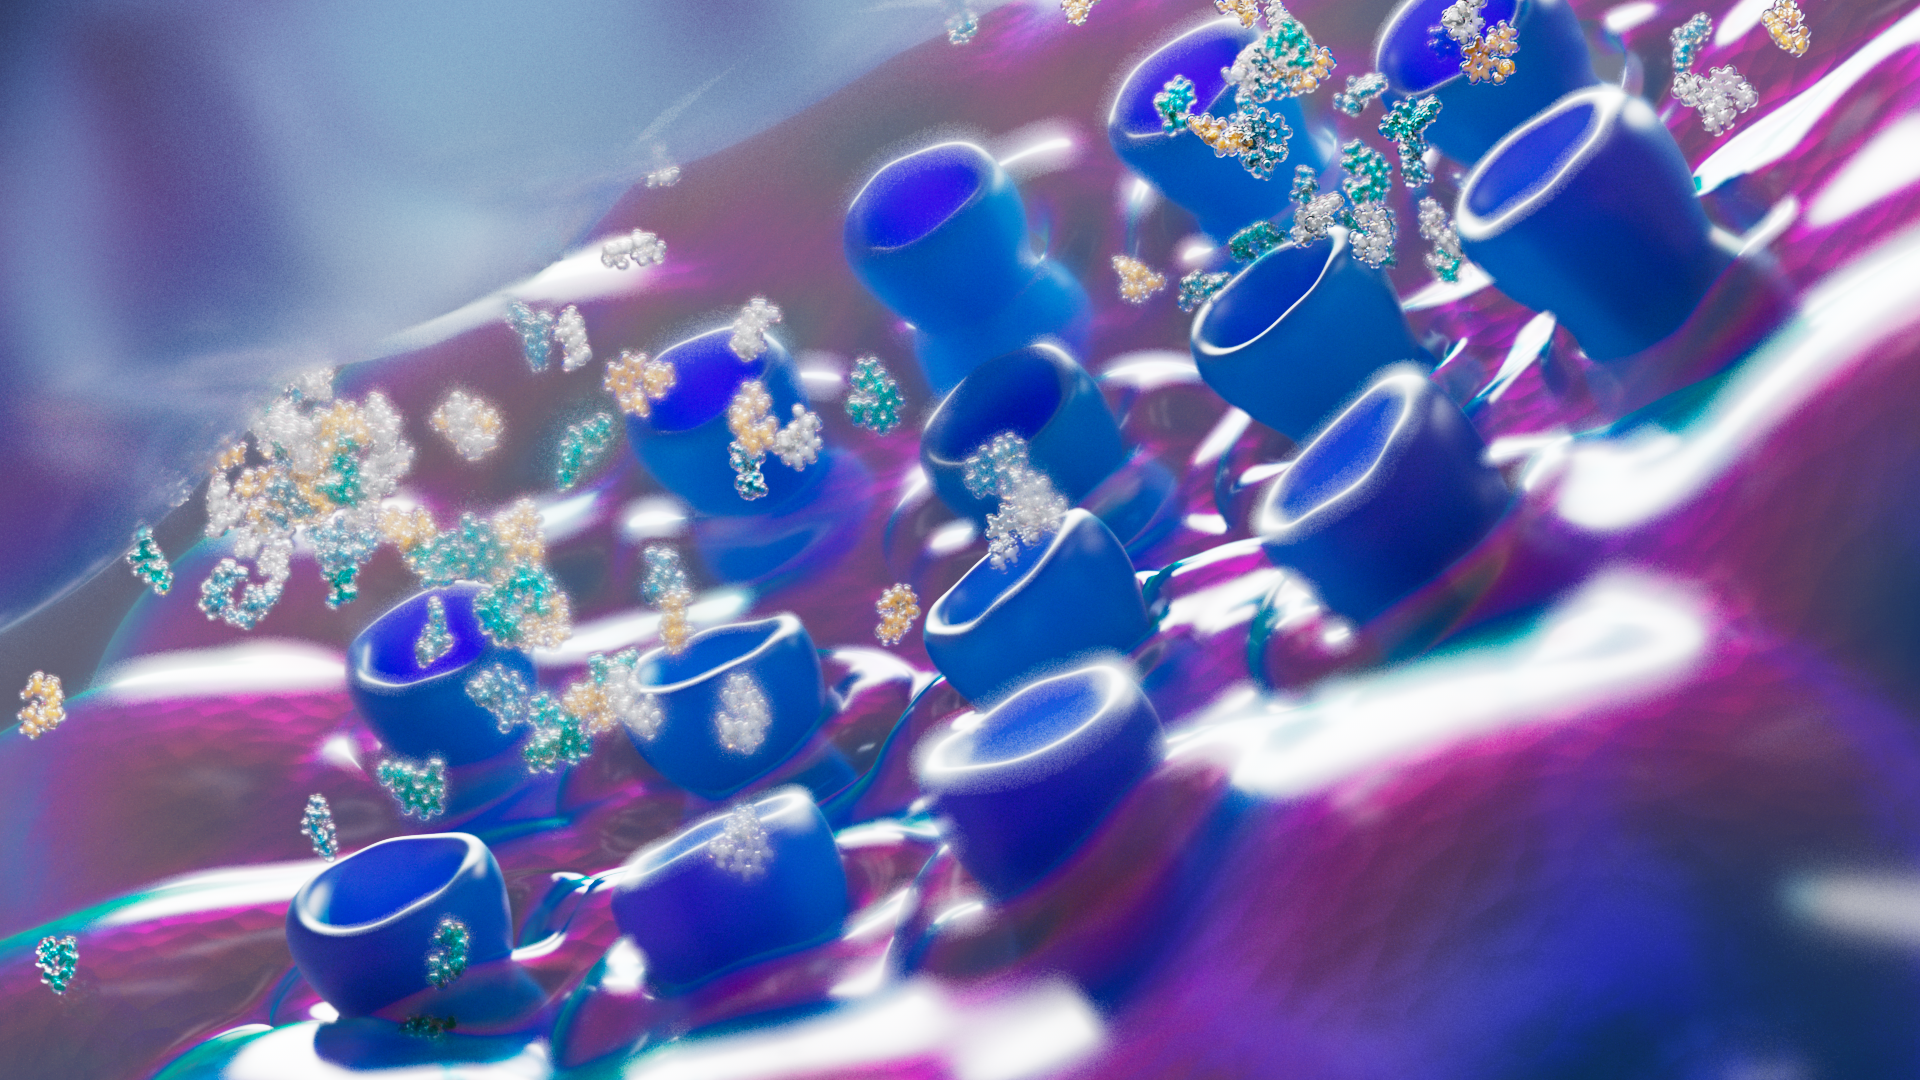

We developed an engaging 3D animation that details the “entourage effect”, a cascade of small molecules inherent to plants and fungi that work in concert to generate positive patient experiences and health benefits.

Style Frames